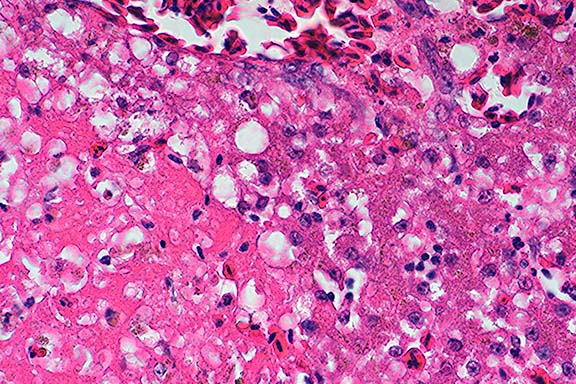

Case 2. Kidney. Note refractile crystalline material replacing tubular epithelium.

Kidney: Degeneration, necrosis, and loss, tubular, diffuse, severe, with intraluminal oxalate crystals, diffuse moderate interstitial fibrosis, and multifocal mild lymphocytic interstitial nephritis, Beefmaster, bovine.

In monogastric animals, ingestion of ethylene glycol (EG) is the most common source of renal oxalosis. Metabolites of EG play the major role in pathophysiology. In the liver, ethylene glycol is metabolized to glycoaldehyde, which depresses respiration and serotonin metabolism and alters CNS amine concentrations. Glycoaldehyde is rapidly metabolized to glycolate, which causes severe metabolic acidosis, and is thought to be the primary toxic metabolite of EG. Glycolate is oxidized to glyoxalate, which is the most toxic metabolite on a per- weight basis; however, its half-life is very short. Glyoxalate inhibits citric acid cycle enzymes and substrate level phosphorylation in mitochondria. Glyoxalate is oxidized to oxalate, which binds with calcium and forms a soluble complex which is filtered by glomeruli. As water is reabsorbed by the tubules and the pH of the filtrate decreases, calcium oxalate precipates to form crystals. This results in nephrosis, and hypocalcemia if enough calcium is complexed. The cause of death is hyperkalemia resulting in cardiac arrest.